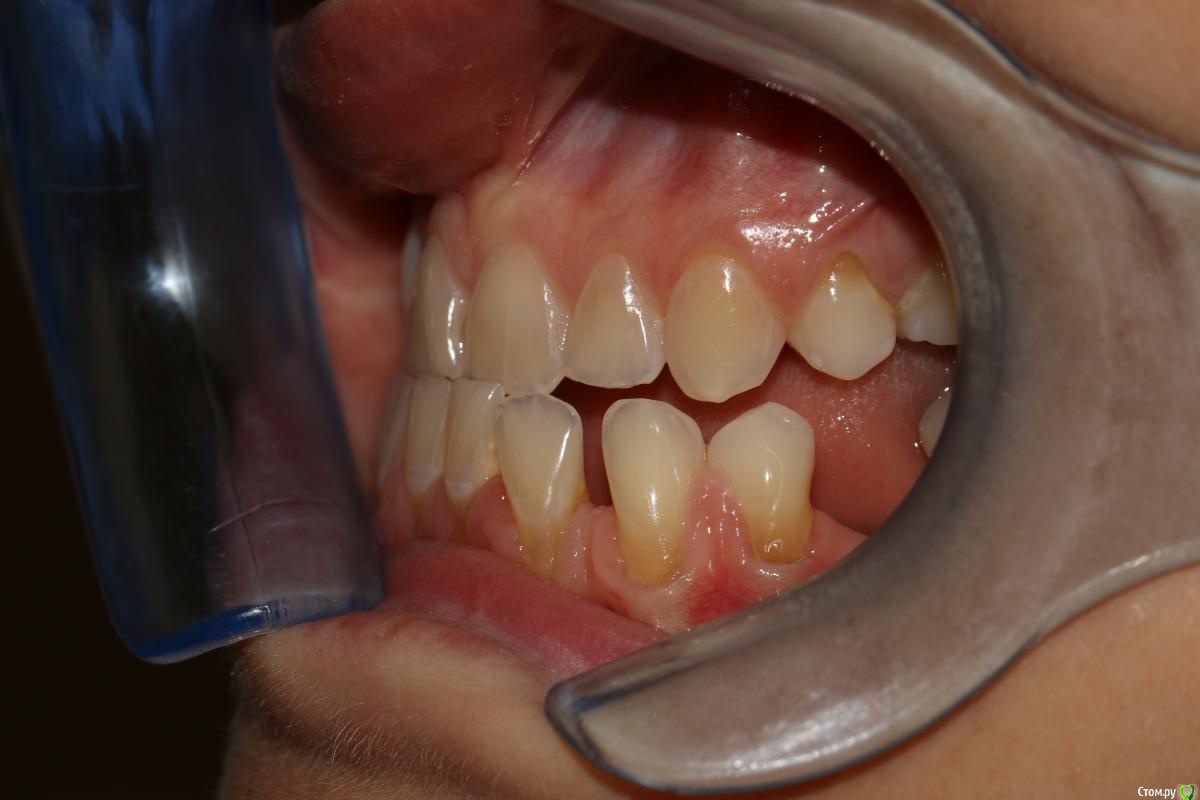

rytovst Опубликовано 15 сентября, 2018 Поделиться Опубликовано 15 сентября, 2018 Здравствуйте ,коллеги!Посоветуйте ,как и чем лучше закрыть данные рецессии перед ортодонтическим лечением.Склоняюсь к расщепленному лоскуту и ССТ с неба + коронально-смещенный лоскут . Может быть взять ССТ с эпителиальной полоской? Ссылка на комментарий

Дмитрий Л. Опубликовано 16 сентября, 2018 Поделиться Опубликовано 16 сентября, 2018 Скажите пожалуйста, а это фото в прикусе...? Какой тут ортодонт диагноз поставил и что планирует делать? Пластика десны перед ортодонтией не всегда показана. Ссылка на комментарий

rytovst Опубликовано 16 сентября, 2018 Автор Поделиться Опубликовано 16 сентября, 2018 -фото ,как вы видите ,не в прикусе ( 6 зубы не смыкаются) -дистальная дизокклюзия - произвести протрузию на нч Ссылка на комментарий

Дмитрий Л. Опубликовано 16 сентября, 2018 Поделиться Опубликовано 16 сентября, 2018 В этом случае, имхо, показания к пародонтологии даже без ортодонтии Я не об этом. Если резцы планируется сдвинуть дистально, то рецессия может уменьшится уже уже от этого, соответственно и успех хирургии будет выше после ортодонтии, а не до. - произвести протрузию на нч Вот честно я не понял здесь вас( Вообще здесь не рецессия, а пародонтит. И устранить нужно причину. Уздечка, преддверие...?+1 за туннель и не уверен по поводу коронарного смещения лоскута: риск порвать лоскут + натяжение от губы только увеличится. Ссылка на комментарий